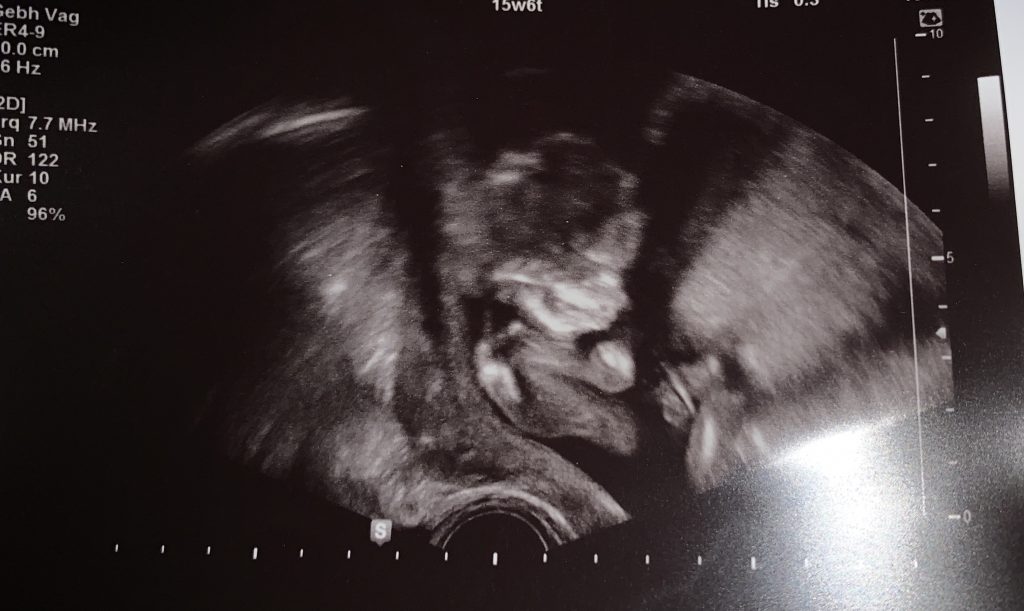

Ich kämpfe immer noch mit Kopfschmerzen, Übelkeit und anderen Unpässlichkeiten aber jetzt darf ich euch erzählen warum. Ich bin nicht krank sondern einfach schwanger. Wir wissen es schon länger und das auch schon ungefähr seit dem ich nicht mehr regelmäßig schreibe, aber wir mussten sichergehen, dass unsere Nummer drei gesund ist. Denn um ehrlich zu sein hätten wir ein weiteres GM1-Kind nicht behalten können. Nicht weil wir es nicht lieben oder wollen, sondern aus dem Grund das wir an unsere bereits vorhandenen Kinder denken mussten. Unsere Lila ist erst 4 und was würde mit ihr passieren wenn sie noch ein Geschwisterlichen bekommt das vermutlich keine 3 wird? Wie wird Remy reagieren, wenn er seinen Platz auf der Couch mit einer weiteren Special Edition teilen müsste? Außerdem waren noch viele weitere Punkte zu beachten, also haben wir eine CVS machen lassen.

Kurz gesagt hat mir am 21.12. eine Gynäkologin eine lange Spritze in den Bauch gestochen und aus dem Mutterkuchen und der Nabelschnur Gewebe entnommen. Es war weniger schlimm als gedacht. Die Probe wurde dann vom Genetiker ins Labor gegeben. Schon vorletzte Woche hatte ich den ersten Anruf, aber leider war die Probe mit meinen Genen kontaminiert, daher mussten weitere Tests gemacht werden. Aber am Mittwoch Abend kam dann der erwartete Anruf. Der Fötus ist nur Träger, das heißt die Krankheit kann nicht ausbrechen. Also ist das Kind gesund. Das einzige was das Kind beachten muss ist, dass es wenn es irgendwann selbst einmal Kinder möchte, seinen Partner/in auch auf GM1 testen lassen muss. Wenn diese/r kein kaputtes Gen hat: super, wenn doch: dann ist es das gleiche Glücksspiel wie bei mir und Sebastian. Also 25% unbetroffenes Kind, 50% Träger, 25% GM1 Kind.

der Neue